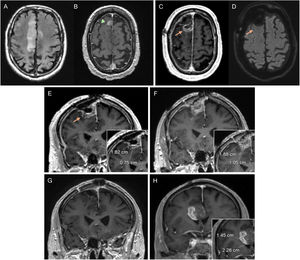

Diagnostic MRI with FLAIR (A) and post-contrast T1-weighted (B) sequences of glioblastoma in the right frontal-parietal region in a 39-year-old male. The post-radiotherapy MRI corresponding to the baseline MRI (C–E) shows a frontal-parietal area with altered FLAIR signal (C) and a contrast-enhancing component (D), with a slight focal increase in the volume in the CBV mapping (arrow) in the DSC perfusion study (E). In the 1st follow-up MRI three months post-concomitant RT and CT (F–H), disease progression is evident, with the finding of an increase of >25% in the contrast-enhancing component (G), which correlates with areas of increased perfusion volume (circle). Additionally, there is a non-measurable uptake component which also shows an increase in volume (arrowheads). Further follow-up MRI (I–K) after the start of bevacizumab shows antiangiogenic agent-related changes in the form of a reduction in the area of signal abnormalities in FLAIR sequences with improvement of the mass effect (I), reduction in the size of the area of contrast enhancement (J) and a tendency towards a return to normal of the volume map (K).

CBV: cerebral blood volume; DSC: dynamic susceptibility contrast magnetic resonance perfusion; MRI: magnetic resonance imaging.

New lesionsTo confirm a change in response category due to the appearance of new lesions, they would have to be ML and automatically mean DP (Figs. 1 and 4). Only if they occur in the period when conMRI is required (less than 12 weeks after the end of RT), new contrast-enhancing or non-enhancing lesions do not automatically mean DP, and we should expect to detect growth of such lesions in the conMRI and that the increase in size corresponds to DP thresholds (Fig. 5).

GB: If DP is suspected on MRI within 12 weeks after RT, conMRI should be performed, as the incidence of PsP is high in this period.32 This conMRI should be performed within four to eight weeks after the suspect MRI, where the changes should be referred to as preliminary progression (PreP). If DP is confirmed on conMRI, the PreP MRI will be the MRI diagnostic of DP (Fig. 5). However, if DP occurs outside the irradiation field, or there is confirmation by pathology, conMRI is not required. Beyond 12 weeks, conMRI would not be necessary (Fig. 4).

Dynamic susceptibility contrast (DSC) magnetic resonance perfusion has proved to be useful in differentiating between post-treatment changes and tumour recurrence, with relative volume being the most consistent parameter13 (Figs. 3 and 5). A consensus of technical and post-processing parameters for DSC perfusion was recently published57 which could be included within the BTIP.